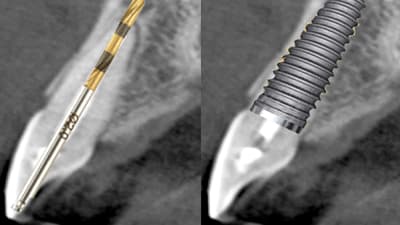

Online Only Implantology Online Only Surgical and Prosthetic Considerations With Immediate Implant Placement By Gregori M. Kurtzman, DDS, Mark Bishara, DDS July 01, 2017 12 min read